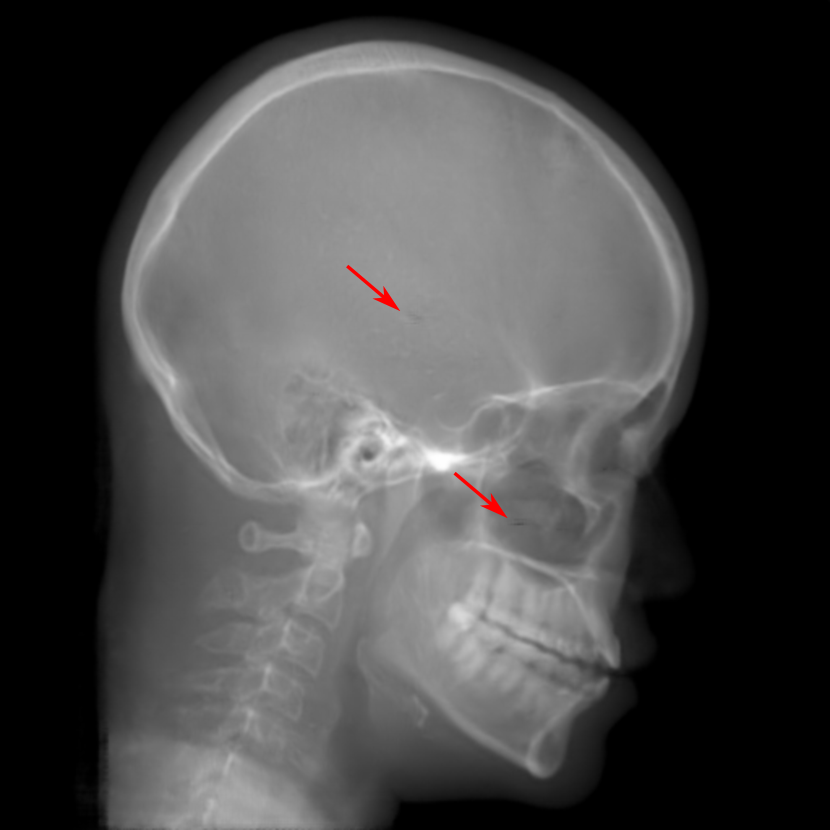

Refer to caption

(a) Reference

(b) 0superscript00^{\circ} perspective

(c) (b)-(a)

7.80, 0.9093

Pix2pixGAN Prediction

(d) 0superscript00^{\circ} Cartesian

(e) 0&180superscript0superscript1800^{\circ}\&180^{\circ} Cartesian

(f) 0&180superscript0superscript1800^{\circ}\&180^{\circ} polar

6.06, 0.9249

2.99, 0.9820

2.07, 0.9842

Pix2pixGAN difference

(g) (d)-(a)

(h) (e)-(a)

(i) (f)-(a)

TransU-Net Prediction

(j) 0superscript00^{\circ} Cartesian

(k) 0&180superscript0superscript1800^{\circ}\&180^{\circ} Cartesian

(l) 0&180superscript0superscript1800^{\circ}\&180^{\circ} polar

6.45, 0.9356

2.36, 0.9864

3.65, 0.9734

TransU-Net Difference

(m) (j)-(a)

(n) (k)-(a)

(o) (l)-(a)

Figure 11: Perspective deformation learning in one exemplary patient case for cephalometric imaging. In (b), the left and right sides of the mandible do not overlap well, as indicated by the arrow. In (c), a scale bar of 2 mm is displayed (zoom in for better visualization), as 2 mm is the clinically acceptable precision for cephalometric landmark detection. In (e), (h) and (j), incorrect areas are marked by the red arrows.

TABLE III: Quantitative evaluation of different methods on head data.

Method Metric 0superscript00^{\circ} input 0superscript00^{\circ} 0&180superscript0superscript1800^{\circ}\&180^{\circ} 0&180superscript0superscript1800^{\circ}\&180^{\circ}

perspective Cart. Cart. polar

Pix2pix RMSE 10.69 7.33 4.58 3.87

GAN SSIM 0.8680 0.9053 0.9476 0.9625

Trans RMSE 10.69 8.13 3.36 3.22

U-Net SSIM 0.8680 0.9257 0.9682 0.9719

The results of one exemplary patient for cephalometric imaging are displayed in Fig. 11. In the 0superscript00^{\circ} perspective projection image (Fig. 11(b)), because of perspective deformation, anatomical structures from the left and right sides do not overlap well, especially for the mandible as indicated by the red arrow in Fig. 11(b). It causes inaccuracy in determining the cephalometric landmark of the gonion. The difference of Fig. 11(b) to the reference Fig. 11(a) is displayed in Fig. 11(c). A scale bar of 2 mm is displayed in Fig. 11(c), as 2 mm is the clinically acceptable precision for cephalometric landmark detection. It is obvious that many anatomical structures in the 0superscript00^{\circ} perspective projection images have position shifts larger than 2 mm. In the prediction image (Fig. 11(d)) using a single 0superscript00^{\circ} view in Cartesian coordinates, perspective deformation is reduced to some degree, as displayed in the difference image Fig. 11(g). For example, the mandible region has less error. However, Fig. 11(g) also indicates that many bony structures still have deviations larger than 2 mm. The results of learning from dual complementary views in Cartesian and polar coordinates are displayed in Fig. 11(e) and Fig. 11(f), respectively. Both images have little perspective deformation, as revealed by their difference images in Fig. 11(h) and Fig. 11(i). Nevertheless, in Fig. 11(e), two dark regions are indicated by the two arrows, which are better visualized in the difference image Fig. 11(h). The results of TransU-Net are displayed in Figs. 11(j)-(o). In Fig. 11(m), the structures near the porion landmark are distorted, for example, the ear canal indicated by the arrow. Consistent with Pix2pixGAN, perspective deformation is largely reduced in the both TransU-Net prediction images using dual complementary views in Cartesian and polar coordinates.